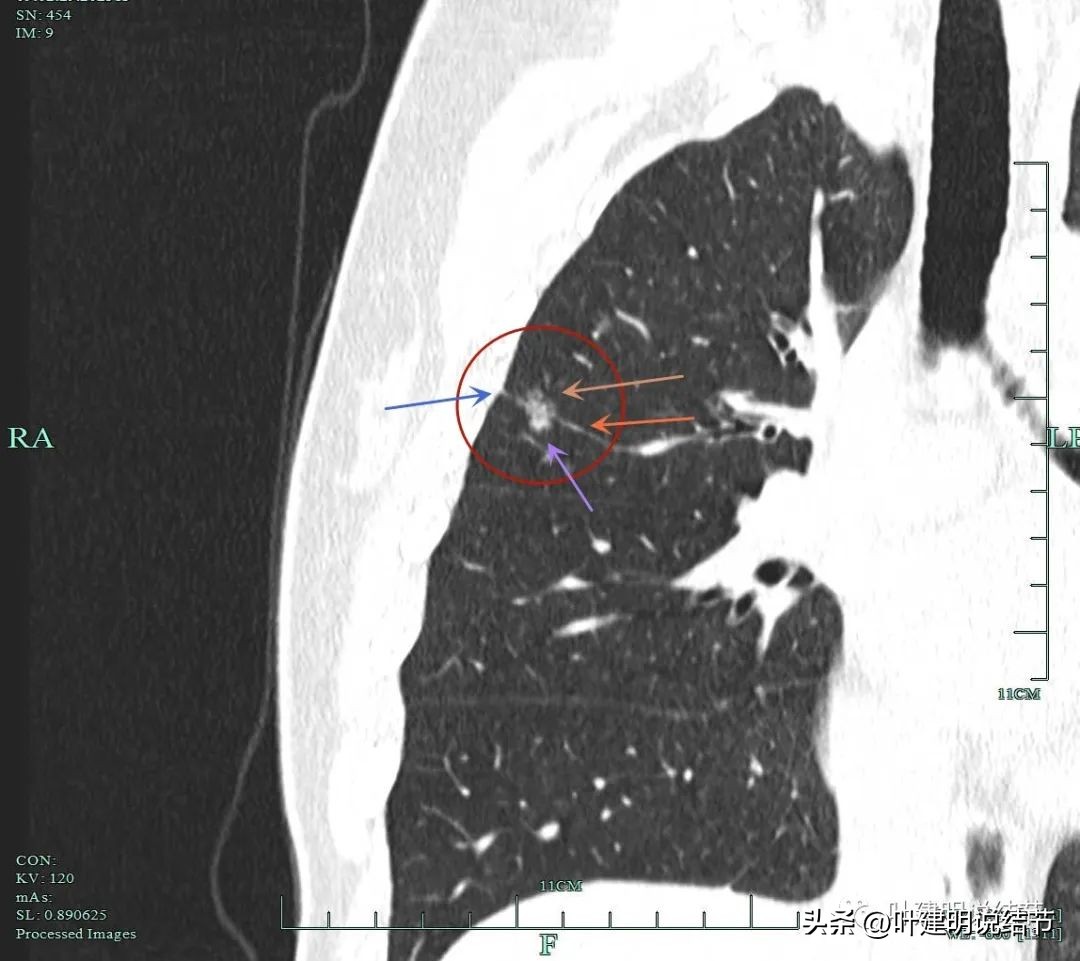

蓝色箭头示月牙铲征;紫色箭头示毛刺或棘突征;桔色箭头示有血管进入并穿行与异常增粗;红色箭头示病灶轮廓与瘤肺边界清楚。

砖色箭头示病灶有分叶征;蓝色箭头示胸膜牵拉;紫色箭头示毛刺征;红色箭头示整体轮廓与瘤肺边界清。总体上看病灶有收缩力、有分叶与毛刺,而且灶内密度不均。是较为典型的浸润性腺癌影像表现。